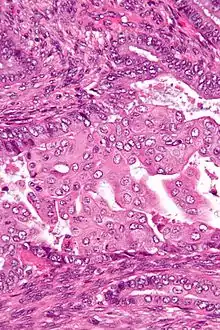

Squamous metaplasia is a benign non-cancerous change (metaplasia) of surfacing lining cells (epithelium) to a squamous morphology.

Squamous metaplasia may be seen in the context of benign lesions (e.g., atypical polypoid adenomyoma), chronic irritation, or cancer (e.g., endometrioid endometrial carcinoma), as well as pleomorphic adenoma.